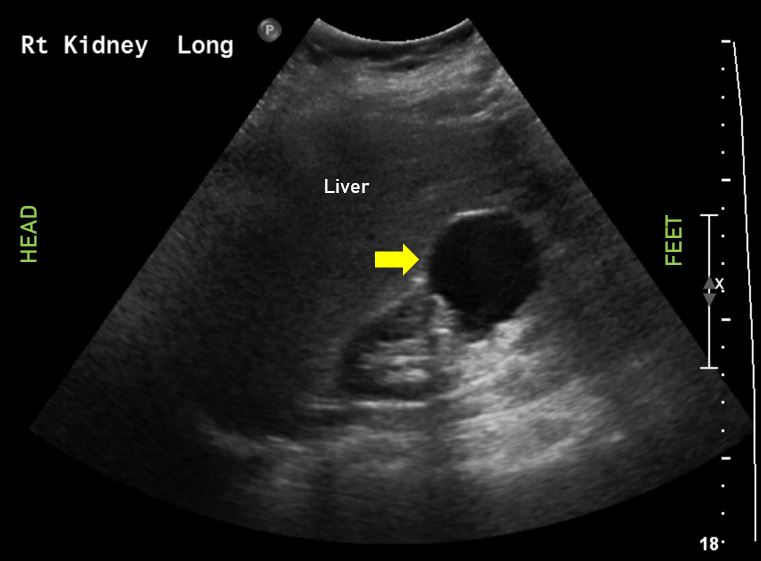

8. kép:

Vese cysta

Egyszerű vese cysta képe a jobb vesében. A vese fölött a máj látható. A vese alsó pólusában megfigyelhető kerek sötét (echoszegény) képlet a vese cysta.